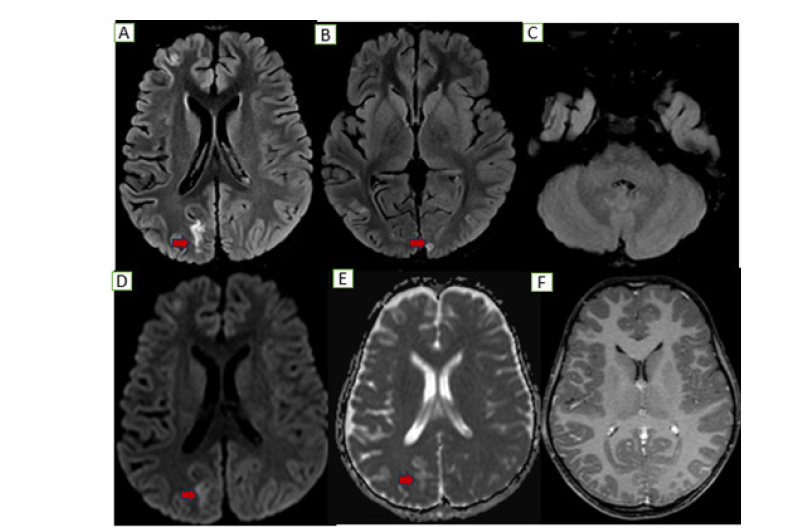

Figure 3:Follow up MRI: Axial sections show near complete resolution of previously seen nodular T2/FLAIR cortical hyperintensities along the left occipital and cerebellar hemispheric regions (B, C) with residual gliotic changes along the bilateral occipital regions (right>left A&B) without no obvious diffusion restriction (D, E) or any post contrast enhancement (F).

An MRI brain showed diffuse gyral edema with T2/FLAIR hyperintensities and diffusion restriction in the bilateral occipital lobes and a tiny focus in the left cerebellar hemisphere (Figure 2). Serology revealed an intermediate positive Brucella IgM and a negative scrub IgM. A CSF analysis showed 110 cells, sugar of 71mg/ dL, and protein of 34mg/dL. Further tests revealed a significantly low serum B12 (158pg/mL), elevated homocysteine (98.7μmol/L), and a high ESR (102mm/hr). The child became afebrile with initial therapy. The confirmation of Brucella exposure led to the addition of septran and rifampicin for a definitive diagnosis of neurobrucellosis. By day 4, her sensorium improved, and she was started on injectable B12 for the deficiency and Vitamin D for associated rickets. She improved gradually on a Rifampicin based triple-drug regimen for 45 days. A follow-up MRI showed residual T2/FLAIR hyperintensities with subtle atrophy but no diffusion restriction, indicating resolved acute inflammation (Figure 3).